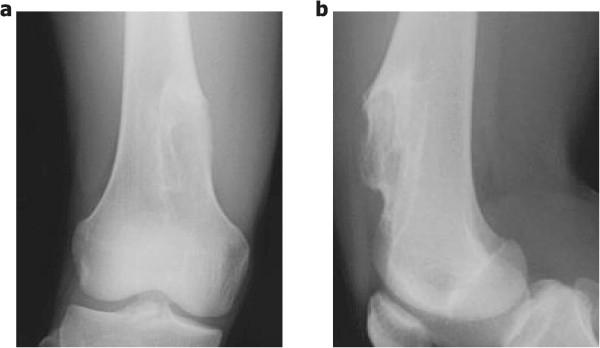

Periosteal chondromas are rare benign cartilaginous tumors that arise adjacent to the cortex beneath the periosteum. These lesions are usually slow-growing and rarely exceed 3 cm in the greatest dimension. Here, we describe a 17-year-old boy who had a giant periosteal chondroma of the right distal femur, which was treated with intralesional resection and intensive curettage. In addition, we report a novel application of a bioresorbable plate in the management of the large bone defect after resection of a benign bone tumor.